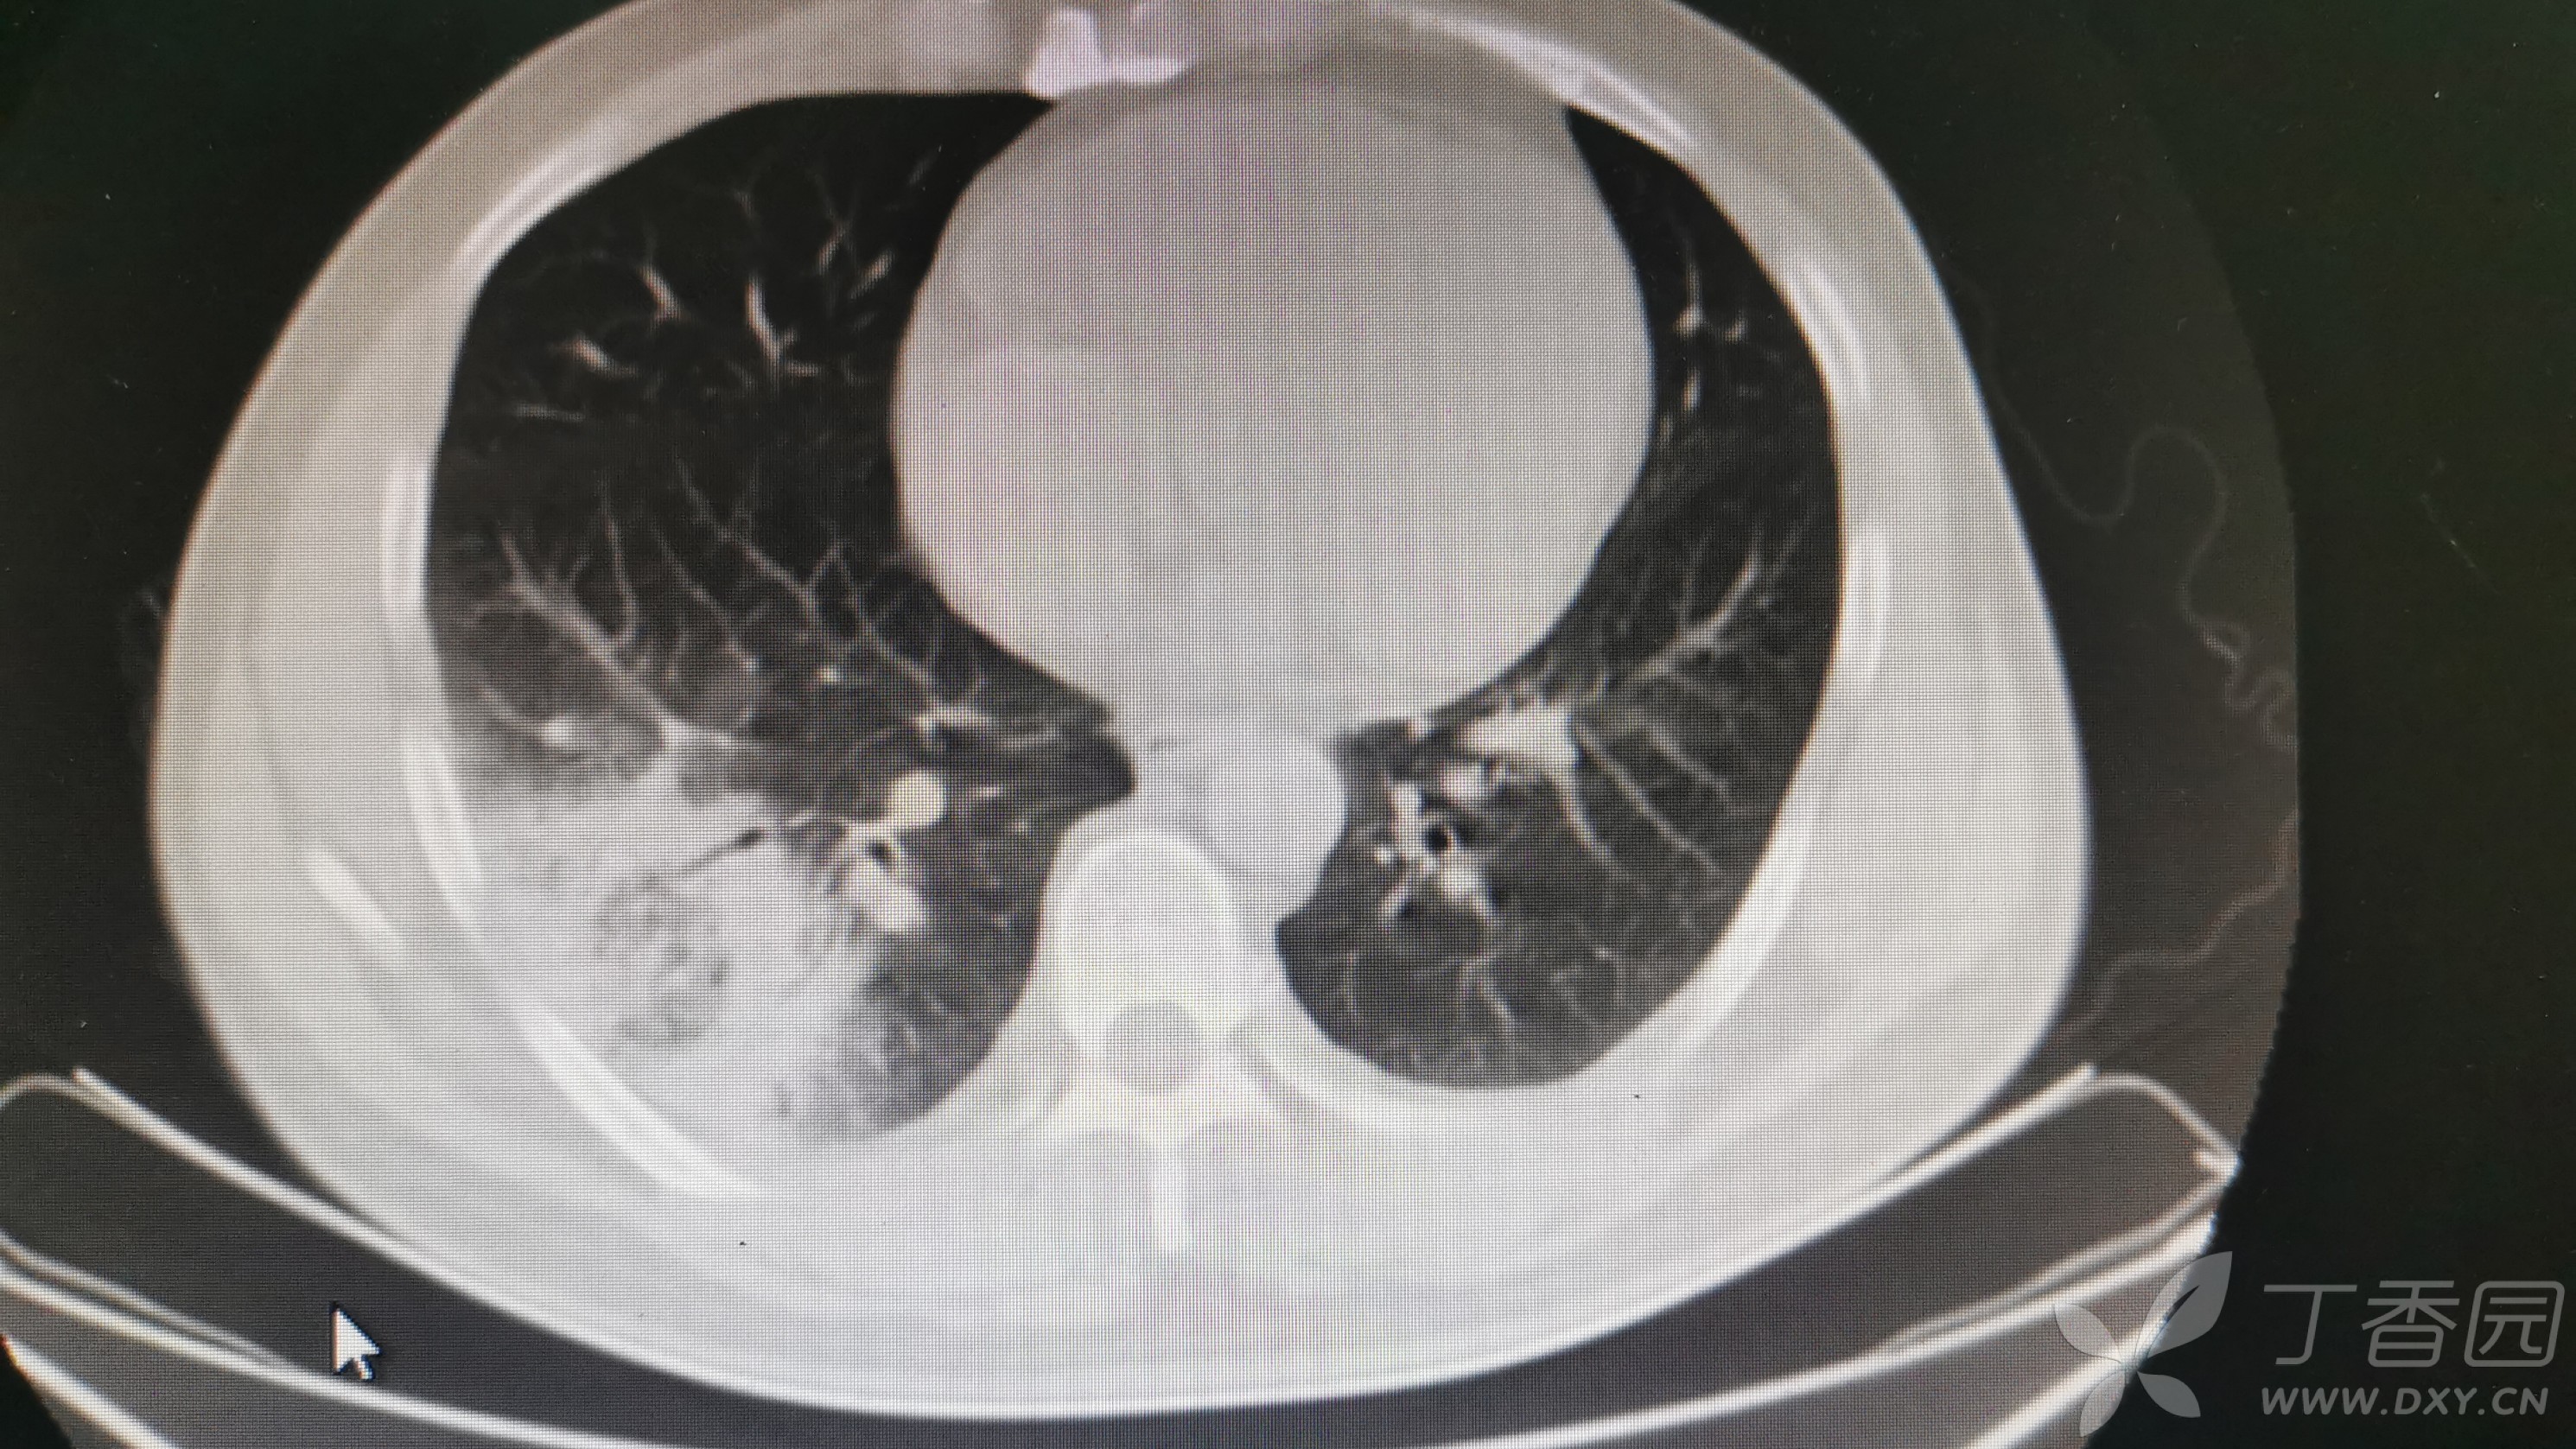

求救,反复发热,干咳7天

G试验阴性,用了头孢他啶+左氧2天,仍有反复发热,最高达39.5摄氏度,头痛、肌肉酸痛好转。

血培养、痰培养都没出结果,考虑啥病原体感染???求抗生素指导

各位老师们,感谢大家的支援!28号早上主任休年假回来一看,说考虑大叶性肺炎,让我把头孢换成了哌拉西林,哌拉没药,所以上的阿莫西林克拉维酸钾1.2g q8h,当天下午就不发热了,真是😭😄🙅♀️🉐